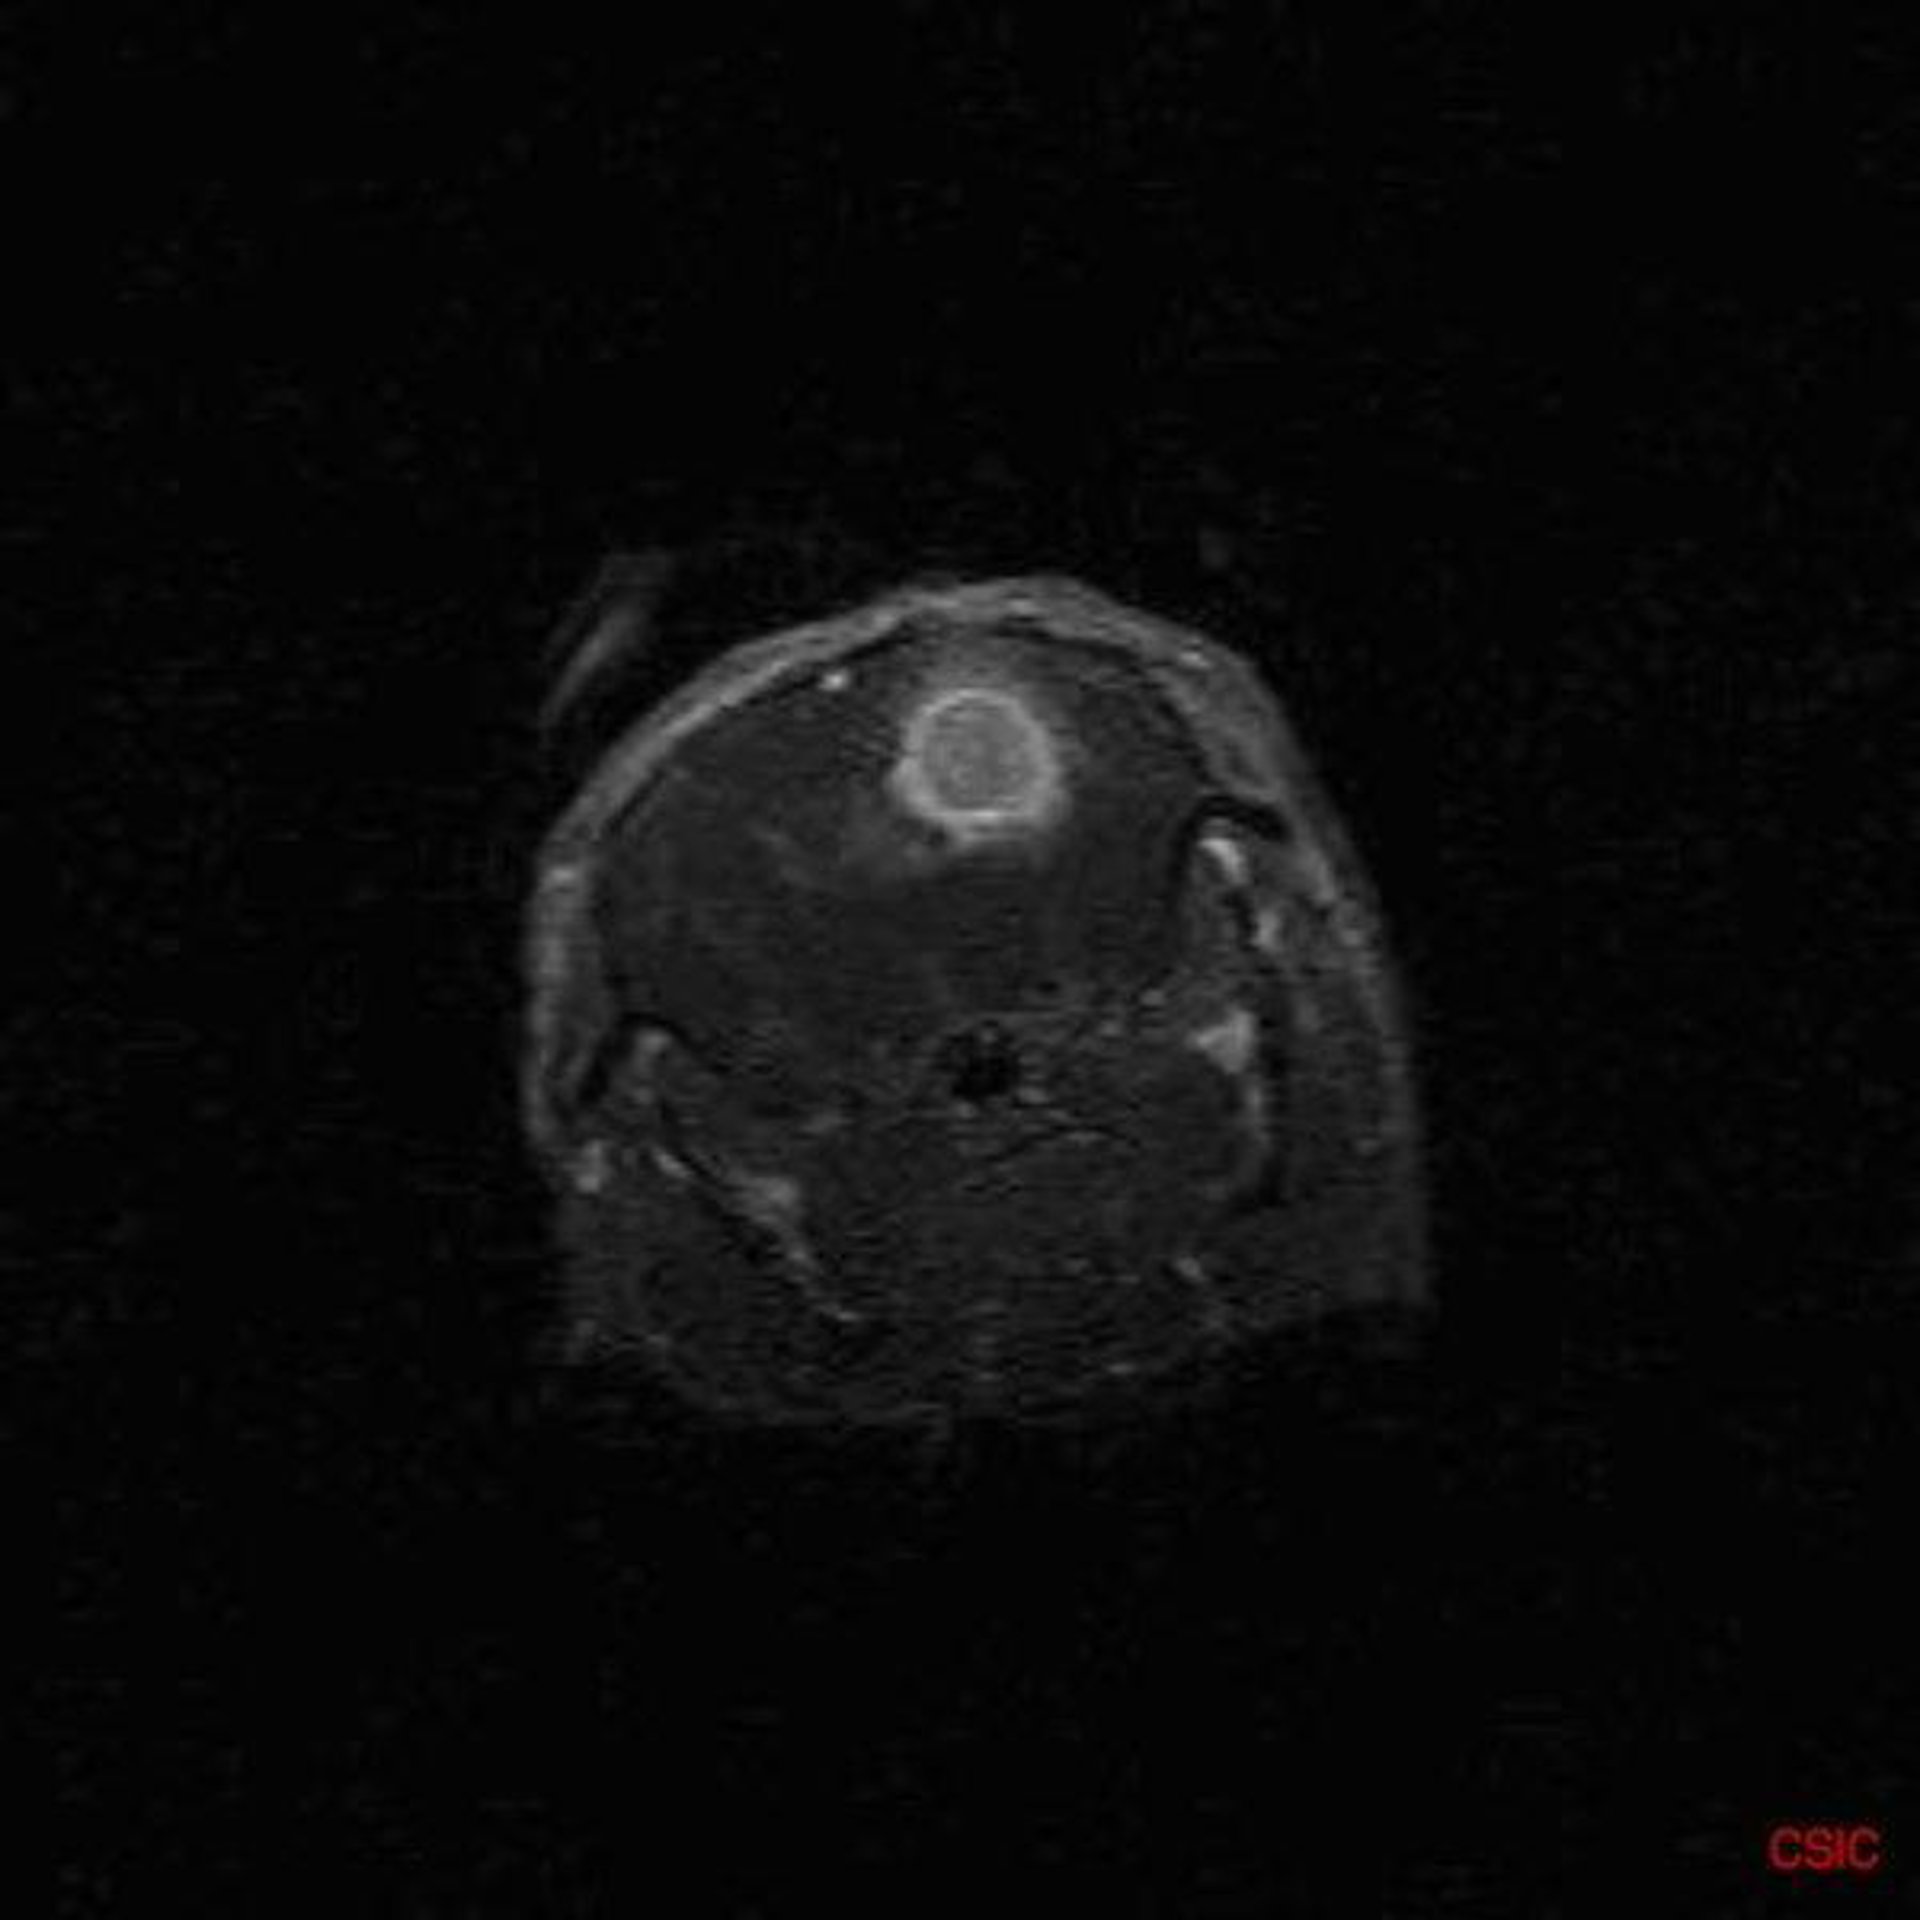

CSIC

Investigadores del Consejo Superior de Investigaciones Científicas (CSIC) y del Centro de Investigaciones Biomédicas de La Rioja han demostrado en ratones que los enfermos de Alzheimer podrían tener una mayor predisposición a padecer cánceres cerebrales primarios

La investigación, publicada en la revista científica 'Oncogene', permitirá avanzar en el conocimiento de los mecanismos celulares y moleculares implicados en el desarrollo de tumores cerebrales primarios, que son aquellos que se originan en el propio sistema nervioso y no como metástasis de otros.

El trabajo no sólo permite conocer más a fondo la enfermedad de Alzheimer, sino avanzar en el conocimiento de los mecanismos celulares y moleculares implicados en el desarrollo de tumores cerebrales primarios (los que tienen su origen en el sistema nervioso), entre ellos el devastador glioblastoma.